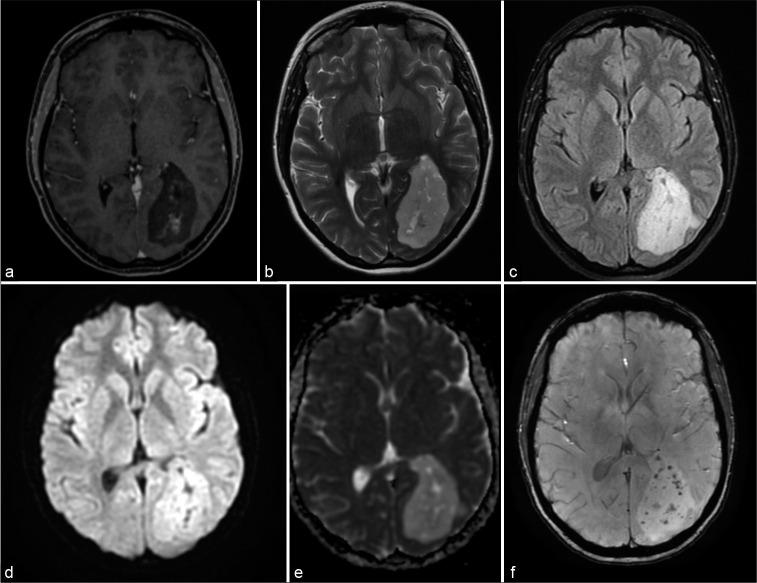

We describe a case of a supratentorial intraparenchymal mass on left occipital lobe in a 26-year-old woman with progressive headache and visual impairment. Differential diagnosis mainly included gliomas, neuronal-glial tumors, ependymoma, and subependymoma. Complete surgical resection was performed and histopathology analysis confirmed diagnosis of subependymoma. Despite its benign behavior the Ki67/MIB-1 labeling index assessed by immunohistochemistry was 5%. After 1 year of follow-up she was free of tumor recurrence.

我们描述了一例26岁女性患者,其左枕叶脑实质内出现幕上肿块,伴有进行性头痛和视力障碍。鉴别诊断主要包括胶质瘤、神经胶质细胞瘤、室管膜瘤和室管膜下瘤。进行了完整的手术切除,组织病理学分析确诊为室管膜下瘤。尽管其生物学行为为良性,但免疫组织化学评估的Ki67/MIB - 1标记指数为5%。随访1年后,她未出现肿瘤复发。